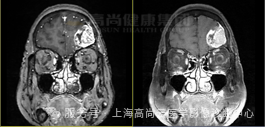

女性,79 岁,因走路不稳 1 天就诊行头颅 CT 平扫示左额叶区混杂密度,占位待除外,建议 MRI 增强检查。两侧基底节区腔隙灶,老年脑。否认药物过敏史。

左额叶见不规则团块状异常信号影,边界欠清,大部分 T1WI 呈稍低、低信号,T2WI 及 T2 FLAIR 呈等稍高信号,内见点片状低信号,DWI 呈高信号,相应区域 ADC 呈稍低信号,ADC 值约 0.793 ×10-3 mm2/s,最大横截面大小约 44 mm×55 mm,病灶后部 T1WI 呈低信号,T2WI 呈高低混杂信号,FLAIR 呈稍低等混杂信号,SWI 呈明显低信号,DWI 以低信号为主,病灶周围见大片水肿信号影环绕,邻近侧脑室明显受压,左额部中线结构略右偏,增强后病灶呈明显不均匀强化,内可见不规则无强化坏死区,强化区域灌注扫描 CBF 增高,MRS 显示局部 Cho 峰明显升高,NAA 峰明显升高,Cho/NAA 比值约 87.02,出现 Lip 峰及 LAC 峰。3D T1WI 增强显示左侧额叶病灶邻近脑膜增厚强化;另外右侧颞窝底部可见小条状强化灶。

高级别胶质瘤(4 级)